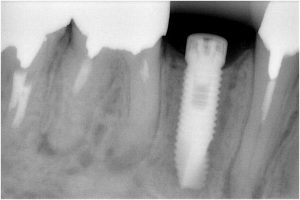

被せ物装着後

川口で精密インプラント治療なら さかえ歯科クリニック